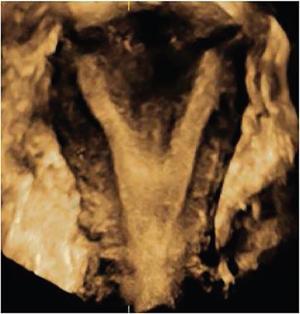

MÜLLERIAN DUCT ANOMALIES Rajani Gorantla Müllerian ducts are a pair of tubular structures that give rise to uterus, cervix, fallopian tubes and upper two-thirds of vagina. Disruption or failure of normal development can result in occurrence of Müllerian duct anomalies (MDAs). These are commonly associated with other congenital anomalies of urinary tract and ovaries due to the close relationship between the development of mesonephric and paramesonephric ducts; few patients also have associated skeletal system anomalies. The prevalence of MDAs in an unselected population was 5.5%; 8% among the infertile women, 12.3% in women with a history of recurrent pregnancy loss and 24.5% in women with miscarriage and infertility. Most of the patients with MDAs are asymptomatic and found incidentally on imaging for any other gynaecological problems, in evaluation of a patient with renal, skeletal or abdominal wall abnormalities. In symptomatic women, complains are related to the type, severity, obstructive anomaly or nonobstructive anomaly. The symptoms can be obstetric or gynaecological related, includes recurrent spontaneous abortions, infertility, preterm labour, intrauterine growth restriction and abnormal foetal lie. Few adolescent girls may present with primary amenorrhoea, hypomenorrhoea, abnormal vaginal bleeding, cyclical pain and mass. Rarely they can present with pelvic inflammatory disease with abnormal vaginal discharge, dyspareunia and urinary tract infections. The female reproductive system develops from a pair of Müllerian or paramesonephric ducts, urogenital sinus and vaginal plate. The ovaries develop separately from the primordial ridge. It is of great importance to understand the normal stages of development, as failure or interruption of any of these stages can lead to a simple to complex spectrum of anomalies. The three stages of Müllerian duct development include: At 6–10 weeks of gestation age, two paired Müllerian ducts and Wolffian ducts formation occurs. When Y chromosome factor (testicular determining factor) is absent, the Wolffian ducts undergo degeneration. The Müllerian ducts further elongate caudally and cross the Wolffian ducts to fuse in the midline. At 10–13 weeks of gestation age, caudal and lateral fusion of the two Müllerian ducts forms primitive uterovaginal canal, which is possessed of solid tissue initially located side by side and further internal canalization leads to the formation of two channels/canals divided by a septum. At this stage, there is reabsorption of the caudal septum and forms single cervical canal and vagina lumen. In around 15–20 weeks of gestation age, complete resorption of the septum takes place in a caudocranial direction from the isthmus to fundus and development of single endometrial cavity results. The fused caudal part of Müllerian ducts gives rise to the uterus, cervix and upper two-thirds of vagina; the unfused cranial part forms the fallopian tubes (Fig. 11.14.1.1). The lower vagina develops from the urogenital sinus, which is separated from the rectum by urorectal septum around 7 weeks of gestation age. The primitive uterovaginal canal embeds into the dorsal wall of urogenital sinus and forms Muller’s tubercle. Around 13 weeks of gestation, two solid masses known as sinovaginal bulbs originate from the upper part of the Muller’s tubercle, further proliferate into the caudal end of the uterovaginal canal to become a solid vaginal plate. Later canalization or degeneration of the central cells of the vaginal plate forms the lower vagina, which is usually completed by 20 weeks’ gestation. The vertical fusion of the upper and lower vagina occurs with resorption of tissue in between and forms single vaginal cavity (Fig. 11.14.1.2). The vaginal lumen is separated from the urogenital sinus by the hymenal membrane. Just before birth, the hymen normally ruptures due to retrogression of the central epithelial cells. However, a thin fold of mucous membrane persists around the vaginal introitus. The ovaries develop separately from migration of primordial germ cells to the genital ridge. Ureteric buds develop separately and concurrently. So renal anomalies are most commonly associated with MDAs with an association of 30%–50%. Various classification systems have been proposed over the past several decades to describe MDAs. Ideally, same classification system needs to be followed by a gynaecologist, surgeon and radiologist for better communication. Buttram and Gibbons classification was suggested in 1979, and it was based upon the level of failure in normal development and segregate the anomalies into groups with similar clinical manifestations, treatment, and prognosis for foetal salvage. According to Buttram and Gibbons, the uterine anomalies were classified into six classes as described in Table 11.14.1.1. The drawback is the lack of classification of vaginal and other anomalies separately. The ASRM (previously the American Fertility Society – AFS) classification system is the most widely accepted classification worldwide over the past years and was introduced in 1988. According to this classification, MDAs are classified into seven classes (class I to class VII) as mentioned in Table 11.14.1.2. However, several limitations have been described by Grimbizis and Campo in 2010 (Fig. 11.14.1.3). The drawbacks of the ASRM classification system are as follows: Hence in 2016, an updated classification of uterine septum, that is ASRM-2016 was proposed and officially approved morphometric criteria are given for distinguishing between septate, normal/arcuate and bicornuate uteri (Table 11.14.1.3). The VCUAM classification was proposed in the year 2005. The main concern is to provide a simple, systematic, clinical classification in addition to providing a precise reflection of the entire malformation. The female genital organs were divided into the following subgroups in accordance with the anatomy: vagina (V), cervix (C), uterus (U) and adnexa (A). Associated malformations were assigned to a subgroup (M) relative to each specific organ. The disadvantage is due to its inherent complexity, and more than 56,700 individual combinations of anomalies are possible. ESHRE and ESGE established a common working group named CONgenital UTerine Anomalies (CONUTA) in order to devise an improved classification system (Table 11.14.1.4). It was published in 2013. Anatomy is the basis for systemic categorization of the MDAs. The subclasses are divided by the different degrees of uterine deformity and their clinical significance (Fig. 11.14.1.4). Cervical and vaginal anomalies are classified into independent supplementary subclasses (Figs. 11.14.1.5–11.14.1.6). For most of the clinicians, it helped as starting point for the development of guidelines for their diagnosis and treatment. The malformations are graded according to severity, U0–U5, C0–C4 and V0–V4, with U5, C4 and V4 being more severe. Class U3 incorporates bicorporeal fusion defects (didelphys and bicornuate) as this was considered as a more functional mode of classification. Arcuate uterus was not included separately, but this is categorized under normal variant into class U1c. Recent studies have demonstrated that the ESHRE/ESGE system provides an effective and comprehensive classification for almost all the currently known MDAs and overcomes the limits of previous classifications. However, there is a relative overdiagnosis of septate uterus with the application of ESHRE–ESGE criteria has been reported and which potentially might lead to unnecessary surgical overtreatment. C0 C1 C2 Normal cervix Septate cervix Double ‘normal’ cervix C3 C4 Unilateral cervical aplasia Cervical aplasia U4 V0 V1 V2 V3 Normal vagina Longitudinal nonobstructing vaginal septum Longitudinal obstructing vaginal septum Transverse vaginal septum and/or imperforate hymen V4 Vaginal aplasia C MDAs’ characterization and classification is of great significance, as the treatment is determined by the type and severity of abnormality. The various imaging modalities available include: HSG was the most recognized imaging modality, earlier to the development of the ultrasonography (USG) and MRI. It is an invasive fluoroscopic-guided procedure for uterine and tubal assessment, and is performed during the midproliferative phase of the cycle, ideally between days 7 and 10 of the cycle when endometrium is thin. Fluoroscopic spot images obtained to evaluate uterine configuration, uterine filling defects and fallopian tube patency. HSG allows evaluation of only the component of the uterine cavity that communicates with the cervix. The anatomic information about myometrium and external fundal contour will not be provided by HSG. The diagnostic criteria used to diagnose MDAs on HSG include: HSG findings of different MDAs are described in Table 11.14.1.5 and Fig. 11.14.1.10. Virtual HSG is a noninvasive technique performed by using a computed tomography (CT) scanner, done 45 s after the contrast material instillation begins. Contraindications are similar to those for HSG and include pregnancy and active pelvic infection. There is no necessity for retraction of the uterus or manipulation of the cervix. The procedure is quick, easy and prophylactic administration of antibiotics is not required. The use of a power injector helps to ensure a steady low pressure of instillation. The procedure is less painful, more comfortable and easily tolerated by patients than conventional HSG. Radiation exposure sometimes requires cervical clamping, which may result in complications such as bleeding and infection. Transabdominal pelvic ultrasound can diagnose uterine anomalies with accuracy rate of 47%. Two-dimensional transvaginal ultrasound (TVUS) has high sensitivity and specificity than transabdominal study and provided some information about external and internal fundal contours. The detection rate is high if the scan is performed in secretory phase due to better visualization of endometrium. Three-dimensional USG shows great accuracy than 2D USG in evaluation of the uterine morphology. The technique of 3D USG varies with different vendors. It displays both the external and internal fundal contours and lower uterine segment by acquisition of single coronal view of uterus (c-view) (Fig. 11.14.1.11). The only disadvantage is that it is transvaginal study and shall not be done in paediatric age group and sexually inactive women. Three-dimensional TVUS has become the first line of screening tool in most of the infertility clinics as it is noninvasive, faster, repeatable, allows storage of volume data and has multiplanar capability for systematic evaluation of the uterine and cervical cavities. The salient features of various Müllerian anomalies on 3D USG are described in Table 11.14.1.6 with images. Three-dimensional ultrasound is combined with sonosalpingography in this technique and provides better delineation of the uterine morphology. It is a less invasive procedure done in proliferative phase with instillation of saline into the uterine cavity and assessment of the uterus will be done. MRI is a universally accepted imaging modality in the documentation of MDAs and accuracy rate of 100% have been reported. MRI provides excellent delineation of both the internal and external uterine anatomies. T2-weighted (T2W) images are the mainstay of pelvic imaging and are performed without fat suppression. T1-weighted (T1W) images are mainly for the haemorrhagic content. The disadvantages of MRI include time-consuming procedure, not cost-effective, large body habitus, pacemakers, recent surgical history and claustrophobia. The current and proposed MRI protocol given by the European Society of Urology (ESUR-MRI protocol) intends a dedicated evaluation of MDAs as mentioned below (Fig. 11.14.1.12): Vaginal anomalies can be accurately diagnosed with the prior administration of the ultrasound gel, to distend vagina (Fig. 11.14.1.13). It will help in better diagnosis of complex vaginal anomalies, like vaginal septations or vaginal duplication. The normal MRI appearance of uterocervical canal and vagina are shown in Fig. 11.14.1.14. Uterine aplasia/hypoplasia/agenesis is class 1 MDA according to ASRM classification and U5 uterine anomaly according to ESHRE classification. It is a formation defect of the paramesonephric ducts with complete or segmental agenesis of uterus and vagina. The incidence rate is around 10%–15% of all MDAs and considered as the most severe form of uterine anomaly. Most of them have complete uterovaginal agenesis with no single completely developed uterine cavity and are associated with Mayer–Rokitansky–Küster–Hauser syndrome (MRKHS). Two types of this syndrome are depicted. The typical form or type A represents the absence or remnants of the uterus, cervix, upper two-thirds of vagina with normal ovaries and fallopian tube (Fig. 11.14.1.15). The atypical form or type B is associated with the abnormalities of the ovaries, fallopian tubes and genitourinary system (Fig. 11.14.1.16). In a few cases (approximately 10%), unilateral or bilateral uterine remnants and with or without endometrial cavity will be seen (Fig. 11.14.1.17). Most of them present with primary amenorrhoea due to complete uterovaginal agenesis and manifest as MRKHS. These patients have normal secondary sexual characteristics due to the preserved normal ovarian function and phenotype. If uterine remnants with functional cavity is present, will present with cyclical pain along with amenorrhoea due to cryptomenorrhoea and haematometra. USG is the first modality for identification of these anomalies, absence of uterus with normal ovaries is diagnostic. But, it is difficult to locate the uterine remnants and cavity due to small acoustic window. MRI is the gold standard and it classifies into uterovaginal agenesis and hypoplasia. If hypoplasia is identified, sagittal and axial sections are taken. These remnants are seen as T2 hypointense tubular structures, located in close relation to ovaries in the adnexa. Once we identify the uterine remnants, it is important to look for the functional endometrial cavity. These will have reduced endometrial and myometrial width. MRI can easily delineate the zonal anatomy due to its high soft tissue contrast resolution. The management of Müllerian agenesis consists of counselling for the patient and her parents. Some patients with MRKHS opt for creation of neovagina for normal sexual life. Various techniques are available. In the presence of a functional Müllerian remnant, regardless of whether it is communicating or not, medical suppression of menses can be initiated and should be followed by laparoscopic removal of the hypoplastic remnant. Unicornuate uterus or hemiuterus is defined as the unilateral uterine development and the contralateral Müllerian duct could be either partially formed or absent. It is a formation defect and the necessity to classify it in a different class than that of uterine agenesis, which is also a formation defect, is due to the existence of a fully developed functional uterine hemicavity. It is considered as class II anomaly according to ASRM classification and class U4 according to ESHRE classification. The frequency rate is around 20% of MDAs. Renal anomalies most often occur in association with unicornuate uterus and usually on the same side of uterine agenesis. Further unicornuate uterus is divided into two subclasses depending on the presence or absence of a functional rudimentary cavity in ESHRE classification: In ASRM classification, unicornuate uterus is divided into four subcategories: Mostly asymptomatic and presence of the noncommunicating uterine remnants will be identified at the time of infertility work up or caesarean section. If a functional cavity is present, the presentation is dysmenorrhoea or haematometra in an adolescent. The common obstetrics-related complications include abnormal foetal lie, intrauterine growth retardation, preterm delivery, placental abnormalities and uterine rupture. Gynaecological complications are ectopic pregnancy and endometriosis due to retrograde menstruation. On imaging, unicornuate uterus is seen as tubular and fusiform or banana-shaped structure at paramedian location, the endometrium is narrow and tapers to the apex with normal myometrial anatomy and reduced uterine volume. The rudimentary cavity or remnants are better depicted on 3D USG (Fig. 11.14.1.18) and MRI. However, MRI is superior to USG due to its high soft tissue resolution. The rudimentary cavity can communicate with main cavity or connected by fibrous band. The nonfunctioning cavity will be seen as T2 hypointense structure with loss of zonal anatomy (Figs 11.14.1.19 and 11.14.1.20), whereas the functioning cavity will show the deformed zonal anatomy (Fig. 11.14.1.21), and its complications like haematometra as T1/T2 hyperintense endometrial collection. Unicornuate uterus without rudimentary cavity does not require any procedure. But in the presence of communicating or noncommunicating rudimentary horn, surgical resection must be considered to prevent complications. Uterine didelphys is a class III MDA based on the ASRM classification and class U3b bicorporeal uterus according to ESHRE classification with an incidence rate of 5% among the uterine anomalies. It is a lateral fusion defect; results from complete failure of the Müllerian duct fusion. Two noncommunicating endometrial cavities with preserved zonal anatomy are seen with separate cervix. According to ESHRE classification, it is defined as external fundal indentation completely dividing the uterine corpus up to the level of external cervical os. It is most commonly associated with longitudinal vaginal septum in around 75% of cases. Some patients may show transverse vaginal septum and these will be obstructive or nonobstructive type. Renal anomalies are also commonly associated with uterine didelphys. Uterine didelphys is usually asymptomatic and diagnosed incidentally on pelvic examination or caesarean section. The uterine didelphys with obstructed vagina (Fig. 11.14.1.22) will present at adolescence as dysmenorrhoea, haematometrocolpos and haematosalpinx. Sometimes retrograde menstrual flow can cause endometriosis and pelvic adhesions. Obstetric-related complications include abortion/foetal growth restriction and poor pregnancy outcome. The uterine didelphys with obstructed hemivagina due to transverse vaginal septum and associated ipsilateral renal agenesis are the manifestations of the syndrome called obstructed hemivagina and ipsilateral renal agenesis anomaly/Herlyn–Werner–Wunderlich (HWW) syndrome (Fig. 11.14.1.23).